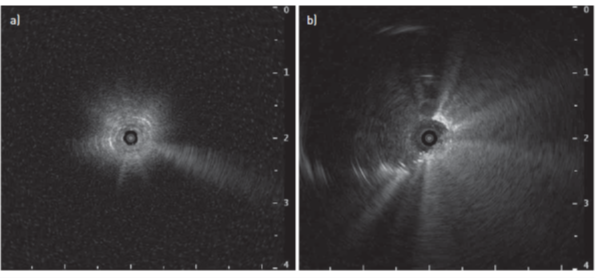

Ved normalt, ventileret og luftfyldt lungeparenkym vil alle ultralydsbølger blive reflekteret, og miniproben producerer et snestormslignende “white-out” ultralydsbillede (figur 1a), selv når læsionen er tæt på spidsen af sonden, men adskilt af et lille mellemliggende luftlag. Hvis læsionen kan nås endobronkialt, og spidsen kan placeres i eller ved siden af læsionen, vil billedet ændre sig (figur 1b).

Figur 1a: “white-out” ultralydsbillede og figure 1b excentrisk tumorslagskygge